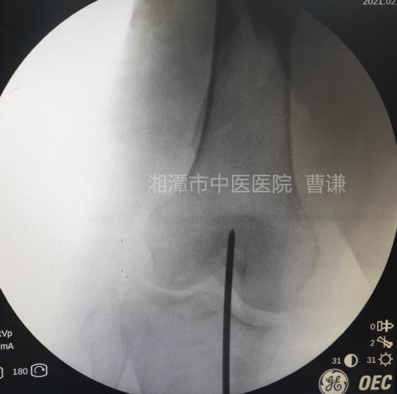

通过正侧位透视进钉点位置,正位位于髁间窝中点稍偏外侧,侧位位于Blumensaat线稍前方。避免损伤后交叉韧带及髓内钉穿出后侧皮质。

扩髓后沿导针置入髓内钉,注意尾端不要突出髁间窝,髓内钉尖端应置于小转子水平。

安装瞄准器后分别置入远端锁钉及近端锁钉,透视锁定良好。

透视侧位骨折对位对线良好,锁钉位置良好。